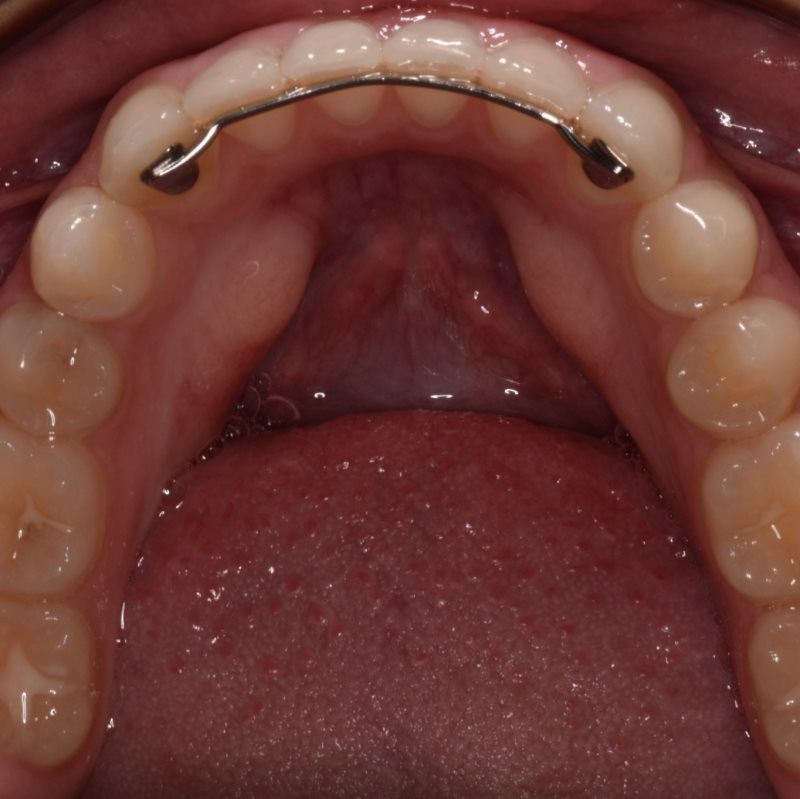

Bonded Retainers

Bonded lingual retainers are cemented directly to the inside surface of your lower canines (eye teeth). This is one of the best ways to prevent your lower teeth from shifting as it is permanently attached. Patients with bonded lingual retainers must be careful with their bite as the bonding material may break due to incorrect biting and cause teeth to shift quickly. As with removable retainers, it is important to keep them clean. When brushing, make sure to carefully clean the inside of your lower teeth as well as the wire.